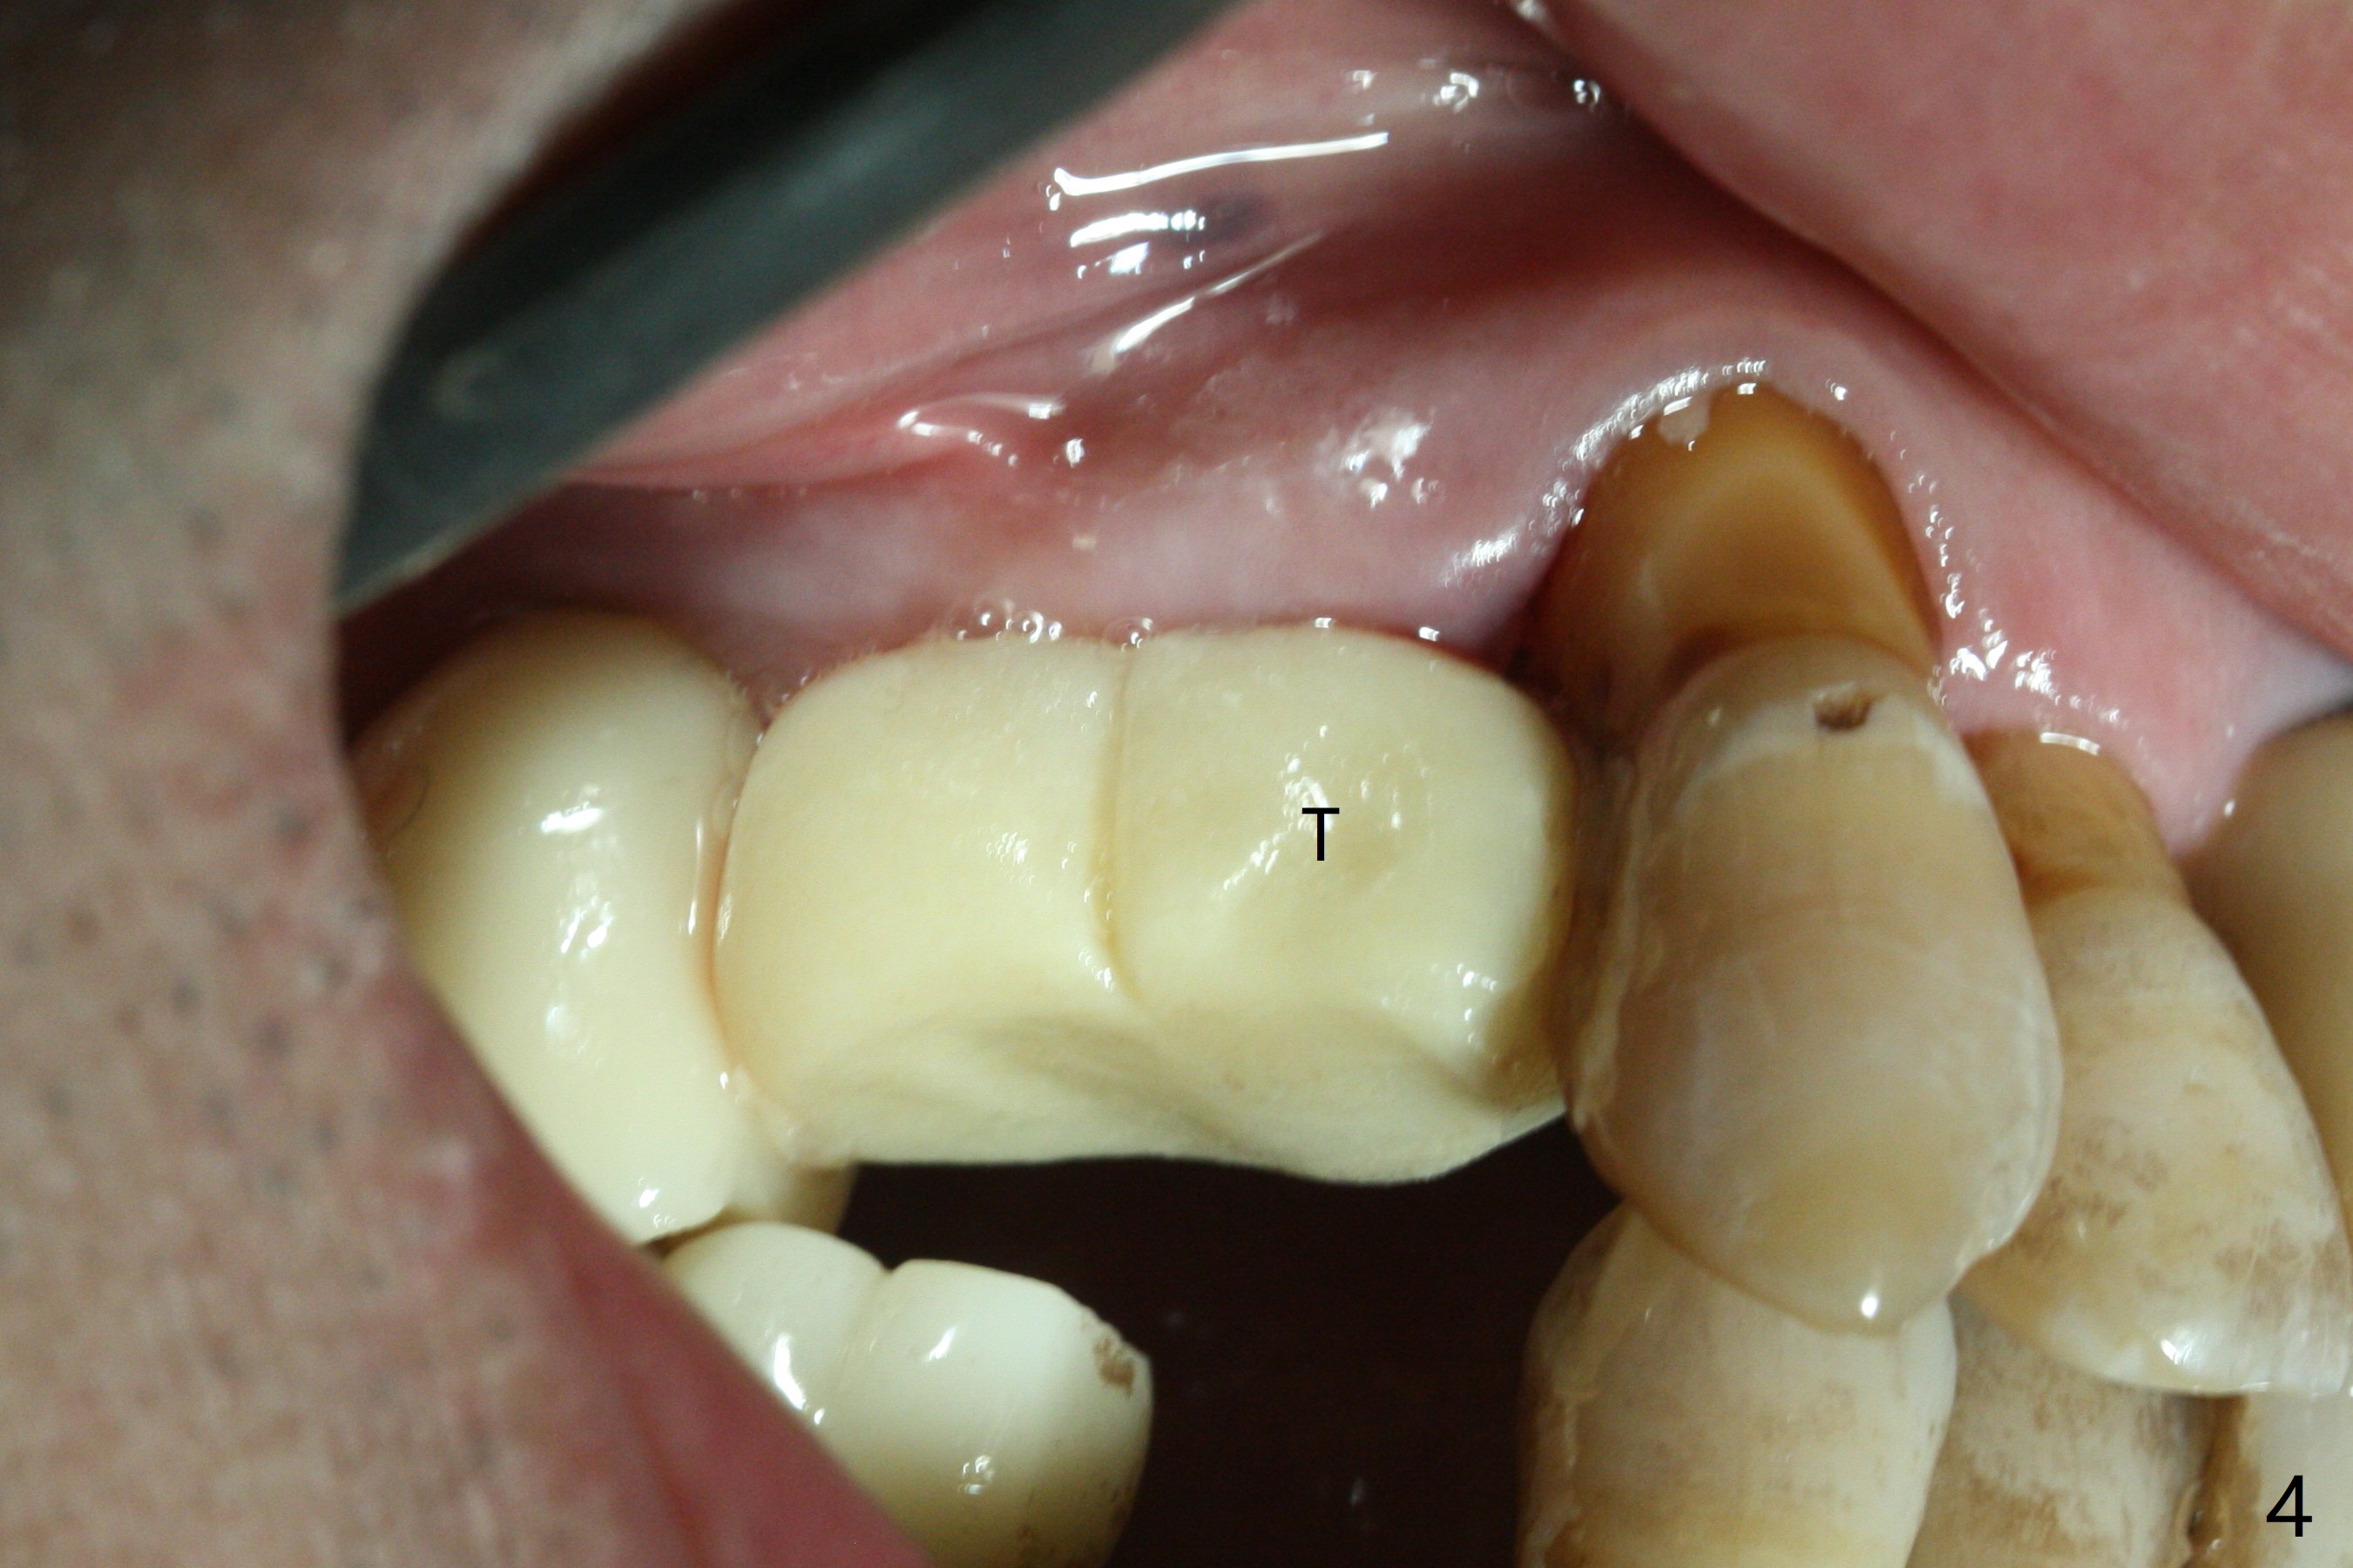

Today schedule is to extract the teeth #4 and 5 and place an implant at #5. When the latter is done, it appears that the implant at #15 should be placed at the same appointment (Fig.1). Once an abutment is placed at #5 (Fig.2 A, 5) for temporary crown (Fig.4 T) , the guide may be not seated again unless the crown is removed. Luckily the implant placement at #15 is quick and smooth with the guide (Fig.3,6). The implants seem to be covered by the bone 4 months postop (Fig.7,8). #15 abutment screw needs retightening because of long crown 1.5 months post cementation. Access hole is palatal. There is premature contact in lateral movement. The buccolingual occlusal table is large at #14 and 15. In fact there is more occlusal contact at #14 than #15 in centric occlusion. Tissue level implants should have been placed to reduce implant/abutment loosening. The incomplete abutment seating (Fig.5,7) is noted after retightening the loose cantilever FPD 1 year post cementation (Fig.9 <). After removal of the FPD, the abutment is reseated completely without interference of the proximal contacts (Fig.10).